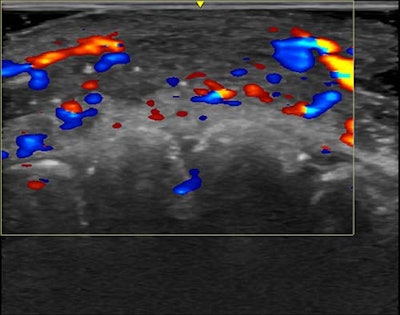

Color Doppler ultrasound shows vascular occlusion from hyaluronic acid fillers. Here, blood flow is absent in a segment of an artery on the lip.RSNA

Color Doppler ultrasound shows vascular occlusion from hyaluronic acid fillers. Here, blood flow is absent in a segment of an artery on the lip.RSNA